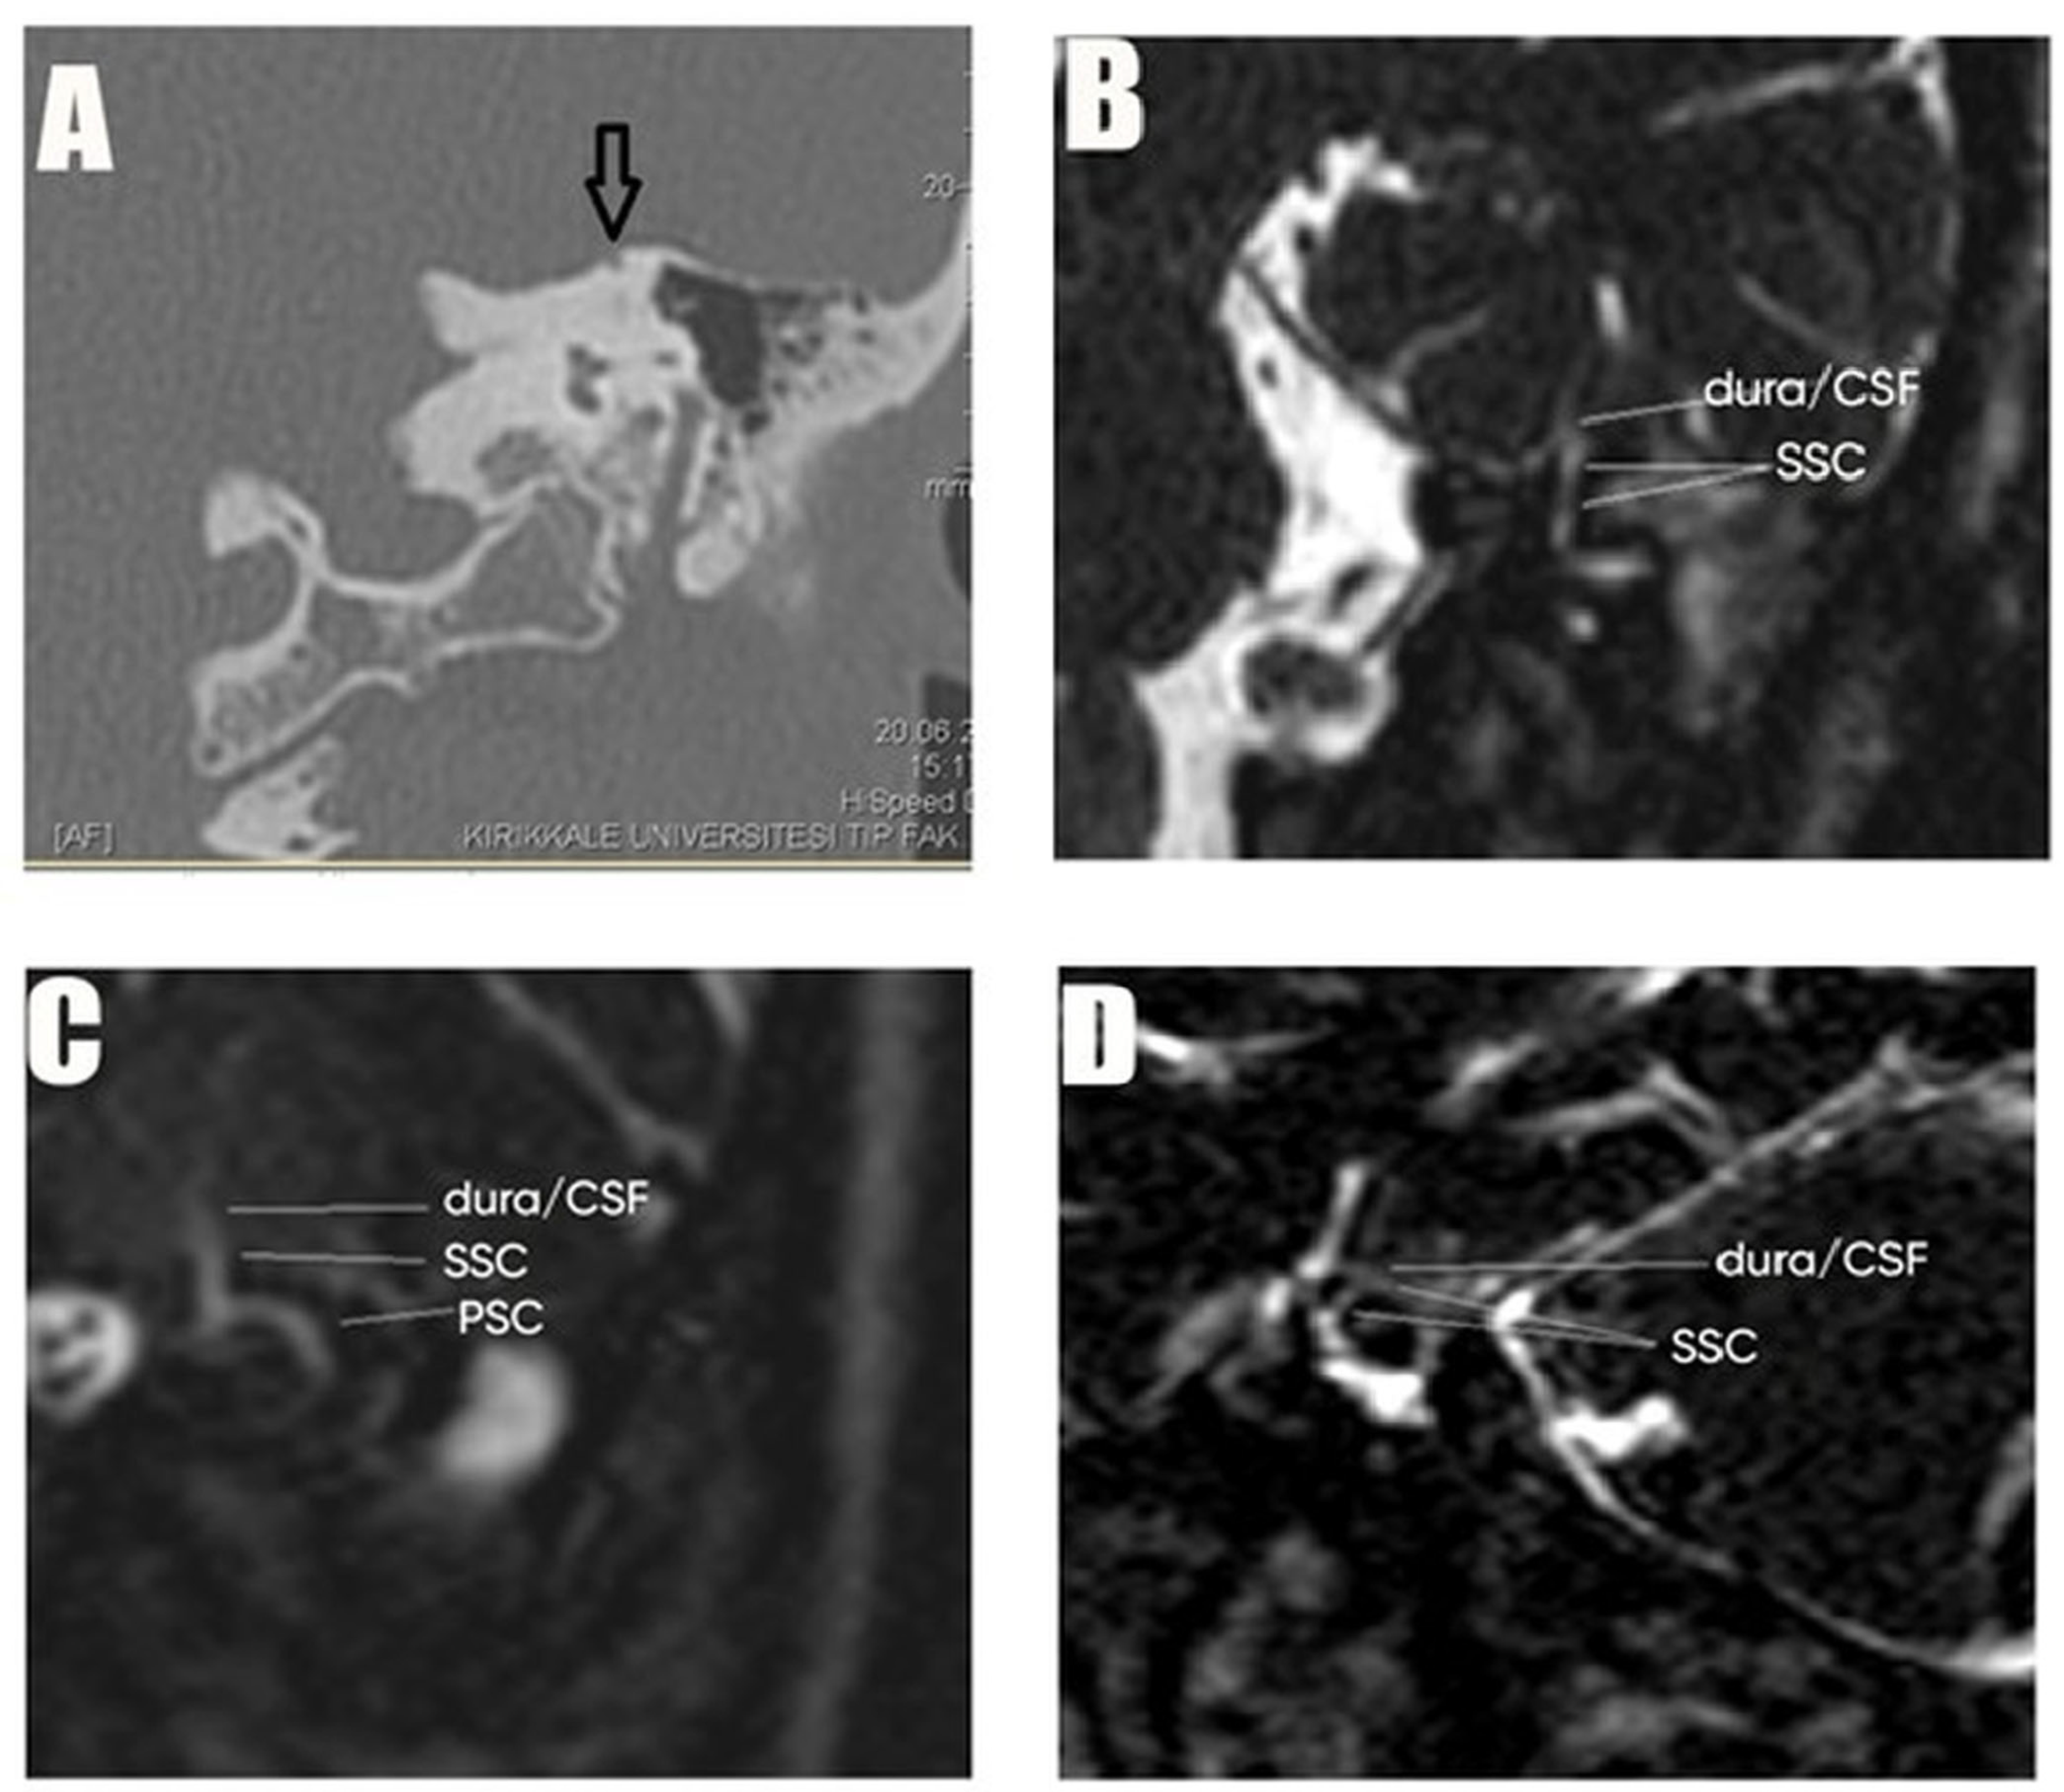

2.2. Study Procedures

2.3. Intervention Protocol or Study Groups